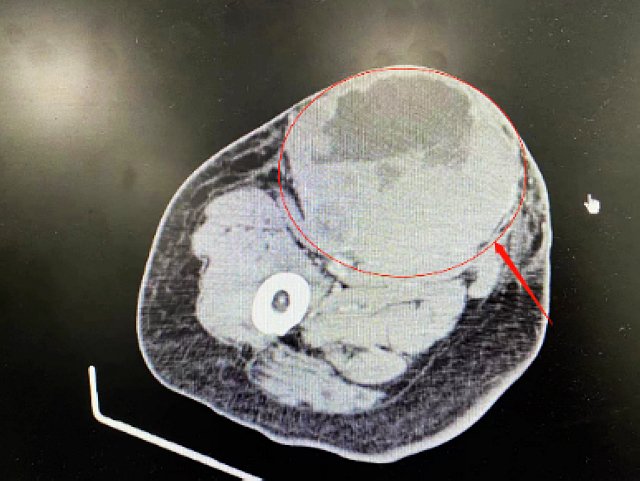

谁知好景不长,唐阿姨病情再次加重。治疗了2个周期后,唐阿姨出现头晕、头痛、反应迟钝的症状,甚至有时神志不清。复查发现颅内肿瘤、右侧大腿皮下肿瘤又迅速增大,右侧大腿皮下肿瘤已经长到了18×14×7cm,局部皮肤破溃、渗血渗液。

治疗前